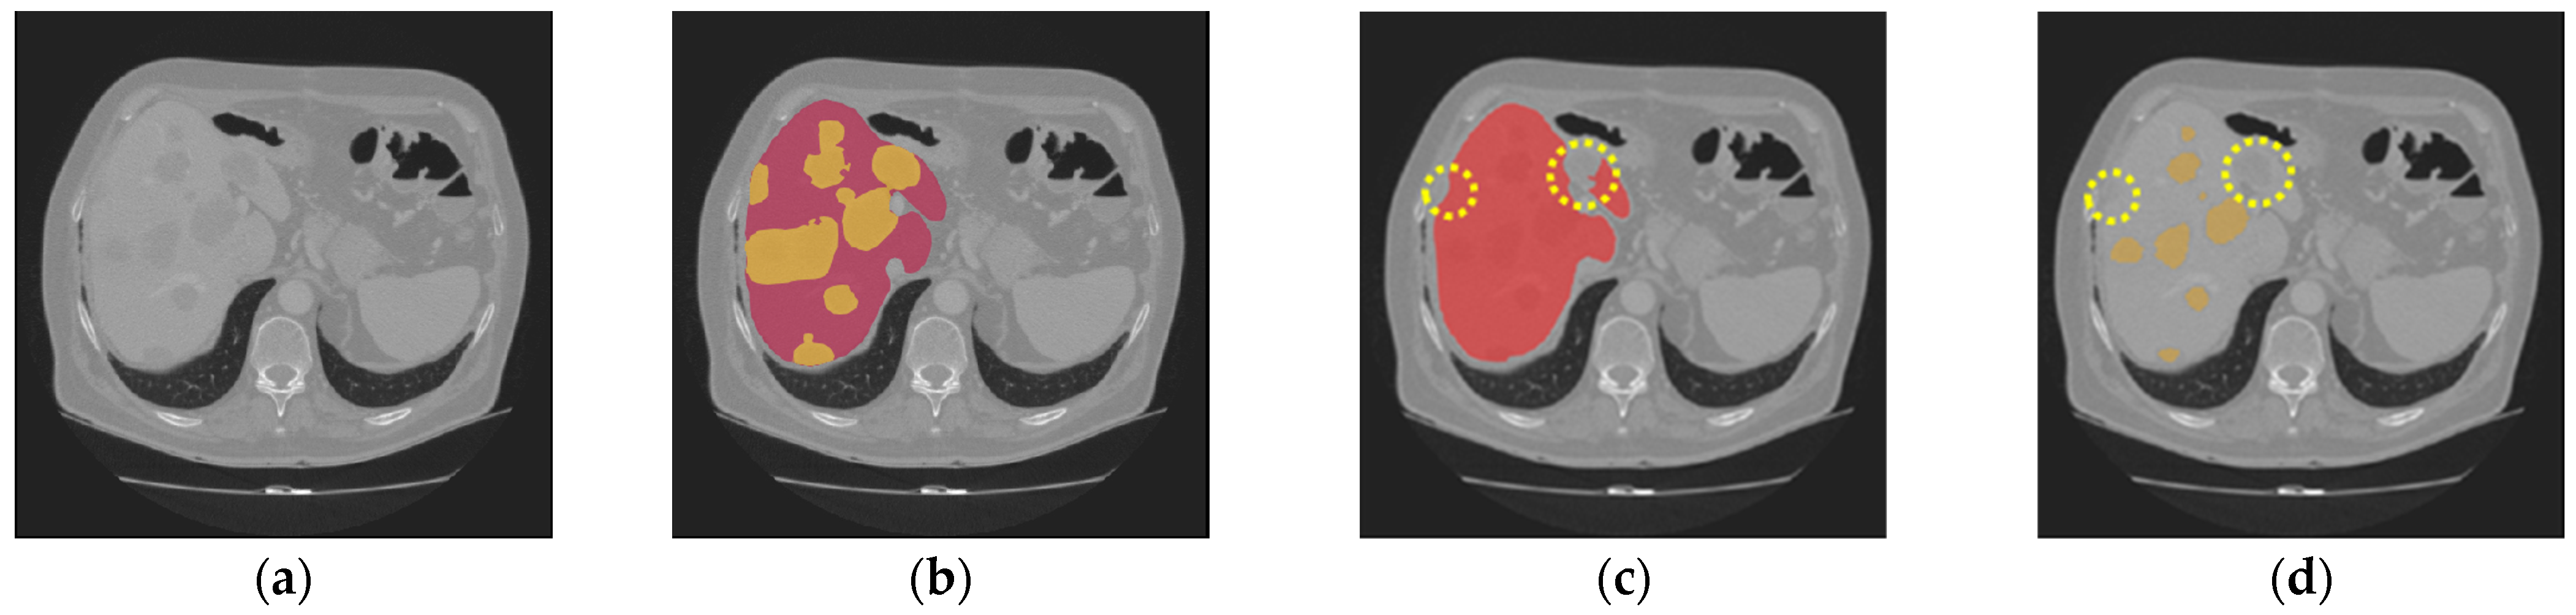

Nevertheless, our study has limitations in certain aspects. The introduction of the two gradient-enhanced encoders increases the complexity level of our model and therefore the computational cost. Furthermore, the tumor segmentation performance can be affected by the liver segmentation performance. The proposed method achieved high performance on both the LiTS dataset and the 3DIRCADb dataset, with an average DSC of 97.38% and 97.50% for liver segmentation, respectively. However, in some cases, tumors may be missing in the segmented liver region, as shown in Figure 9c. Then, in the masking step, those tumors will be excluded from the CT images masked by the extracted liver region, which will be used as the input for tumor segmentation. In that case, those tumors will be missing in tumor segmentation, as shown in Figure 9d. In addition, our model may occasionally miss segmenting some extremely small tumors, as shown in Figure 10. This could be caused by tumor size imbalance and biased annotation for small lesions in the public datasets used for our model development. For our future work, the proposed two-step liver tumor segmentation pipeline can be reduced to a single-step pipeline by applying an end-to-end framework. This would enable a direct extraction of tumors from the original CT scans, thereby reducing computational costs and potentially enhancing the robustness of the segmentation process. Furthermore, the sizes of the datasets used for model training and evaluation are relatively small. To strengthen the experimental validity, the performance of the proposed model needs to be further evaluated using k-fold cross-validation or a larger dataset. Lastly, the ablation study is limited in scope and primarily focuses on the effect of post-processing. Though the ablation study in our previous work [19] concluded that the inclusion of the proposed gradient-enhanced encoders and a hybrid loss function that incorporates the HD loss are effective in improving the performance of liver segmentation, their effects on liver tumor segmentation were not studied in the current study. For future work, a comprehensive ablation study that analyzes the impacts of the gradient-enhanced encoders, the proposed hybrid loss function, and the EPA blocks on improving liver tumor segmentation performance will be conducted.

Figure 9. The following are missing in the final tumor segmentation results due to the missing tumors in liver segmentation results: (a) the original CT slice; (b) the ground truth for the liver (red) and tumors (orange); (c) the liver segmentation result with two tumors missing (highlighted in dotted circles); (d) the tumor segmentation results (orange) with two tumors missing (highlighted in dotted circles).